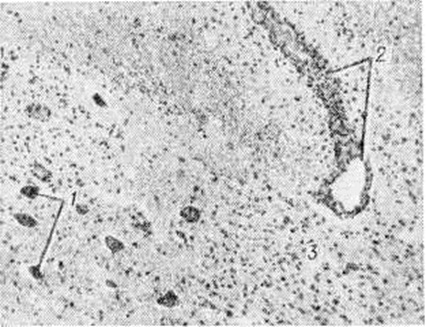

МиелополирадикулоневритМиелополирадикулоневрит (греческий myelos костный мозг+ poly [s] многочисленный + латынь radicula корешок + греческий neuron нерв + -itis) — распространённый воспалительный процесс, охватывающий спинной мозг, корешки и периферические нервы. Интенсивность процесса в указанных отделах различна. В ряде случаев сильнее поражается спинной мозг, в других — корешки и периферические нервы. Миелополирадикулоневрит не имеет нозологической самостоятельности, может возникать при инфекционных, аллергических заболеваниях нервной системы, а также при интоксикациях и энзимных дефектах. Миелополирадикулоневрит может также наблюдаться при вирусных заболеваниях нервной системы: остром рассеянном энцефаломиелите, опоясывающем лишае, полиомиелитоподобных заболеваниях, вызванных энтеровирусами (Коксаки, ECHO), клещевом энцефаломиелите, паралитических формах бешенства. Миелополирадикулоневрит иногда возникает при тяжёлом течении детских инфекций, например, при кори, ветряной оспе, эпидемическом паротите. Миелополирадикулоневрит инфекционно-аллергического генеза встречается после различных вакцинаций (антирабические, противооспенные прививки), после гриппа, при узелковом периартериите. Миелополирадикулоневрит могут быть проявлением бластоматозных процессов (например, миеломной болезни, лейкозов, лимфогранулематоза), глистных инвазий (шистосоматоза). Патологическая анатомия. В основе Миелополирадикулоневрит лежит своеобразный воспалительный процесс, охватывающий серое и белое вещество спинного мозга (смотри полный свод знаний), оболочки, паренхиму и строму спинномозговых корешков и периферических нервов (смотри полный свод знаний). Воспалительный процесс сочетается с очагами демиелинизации (рисунок 1) в различных отделах белого вещества спинного мозга, а также в корешках и периферических нервах. Демиелинизация происходит вокруг сосудов—так называемый перивенозная демиелинизация. Наблюдается лимфоидная инфильтрация стенок сосудов, происходит периваскулярный распад миелина, накопление жира в макрофагах. Помимо перивенозной демиелинизации, формируются очаги микронекрозов со слабо выраженной воспалительной реакцией. Основная масса нервных клеток спинного мозга сохраняется, они гибнут преимущественно в очагах демиелинизации (рисунок 2). Глиальная пролиферация отмечается в перивенозных очагах и сером веществе спинного мозга. Воспалительная реакция в оболочках выражена нерезко и носит вторичный характер. В корешках и периферических нервах наблюдается очаговая сегментарная демиелинизация и пролиферация леммоцитов (шванновской глии);вторичная дегенерация аксона (при гибели нервных клеток), в эндопериневрии инфильтрация стенок сосудов лимфоидными клетками и гистиоцитами. Постоянно отмечается отёк эпидурального пространства и эндо и периневрия корешков. Клиническая картина полиморфна. Основные признаки: болевой синдром, двигательные нарушения, расстройства чувствительности, нарушения функции тазовых органов, изменения цереброспинальной жидкости. Указанные явления возникают либо на фоне симптомов инфекционных заболевания (повышение температуры, головные боли, боли в пояснице, общее недомогание и другие), либо спустя 1—3 недель после перенесённой инфекции. Первые признаки Миелополирадикулоневрит — боли (спонтанные в конечностях), симптомы натяжения, парестезии, дизестезии (смотри полный свод знаний Чувствительность, расстройства). Одновременно или несколько позже возникают двигательные нарушения в виде парезов и параличей (смотри полный свод знаний Параличи, парезы), возможен паралич дыхательных мышц. На фоне общей мышечной гипотонии может отмечаться повышение тонуса отдельных групп мышц. В начальной фазе болезни может наблюдаться повышение сухожильных рефлексов (смотри полный свод знаний), позже возникает арефлексия (смотри полный свод знаний). Патологический рефлексы (смотри полный свод знаний Рефлексы патологические), клонусы (смотри полный свод знаний) отмечаются в начальной стадии болезни и в фазе восстановления двигательных функций. Расстройства чувствительности при Миелополирадикулоневрит постоянны и разнообразны: сегментарно-проводниковые грамм диссоциированные с преимущественным нарушением глубокой чувствительности. При исследовании цереброспинальной жидкости в остром периоде выявляется лимфоцитарный цитоз и умеренное повышение белка, в более поздних стадиях — белково-клеточная диссоциация. |

Рис. 1. | ||